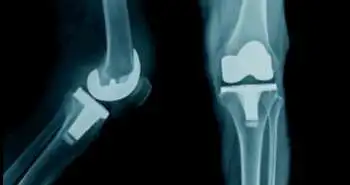

Impact of oral osteoarthritis therapy usage among other risk factors on knee replacement (KR): a nested case-control study using the Osteoarthritis Initiative cohort

The present case-control study was aimed to determine the relatedness between exposure to commonly used oral OA therapies and relevant confounding risk factors related to the occurrence of knee replacement (KR), using the Osteoarthritis Initiative (OAI) database.